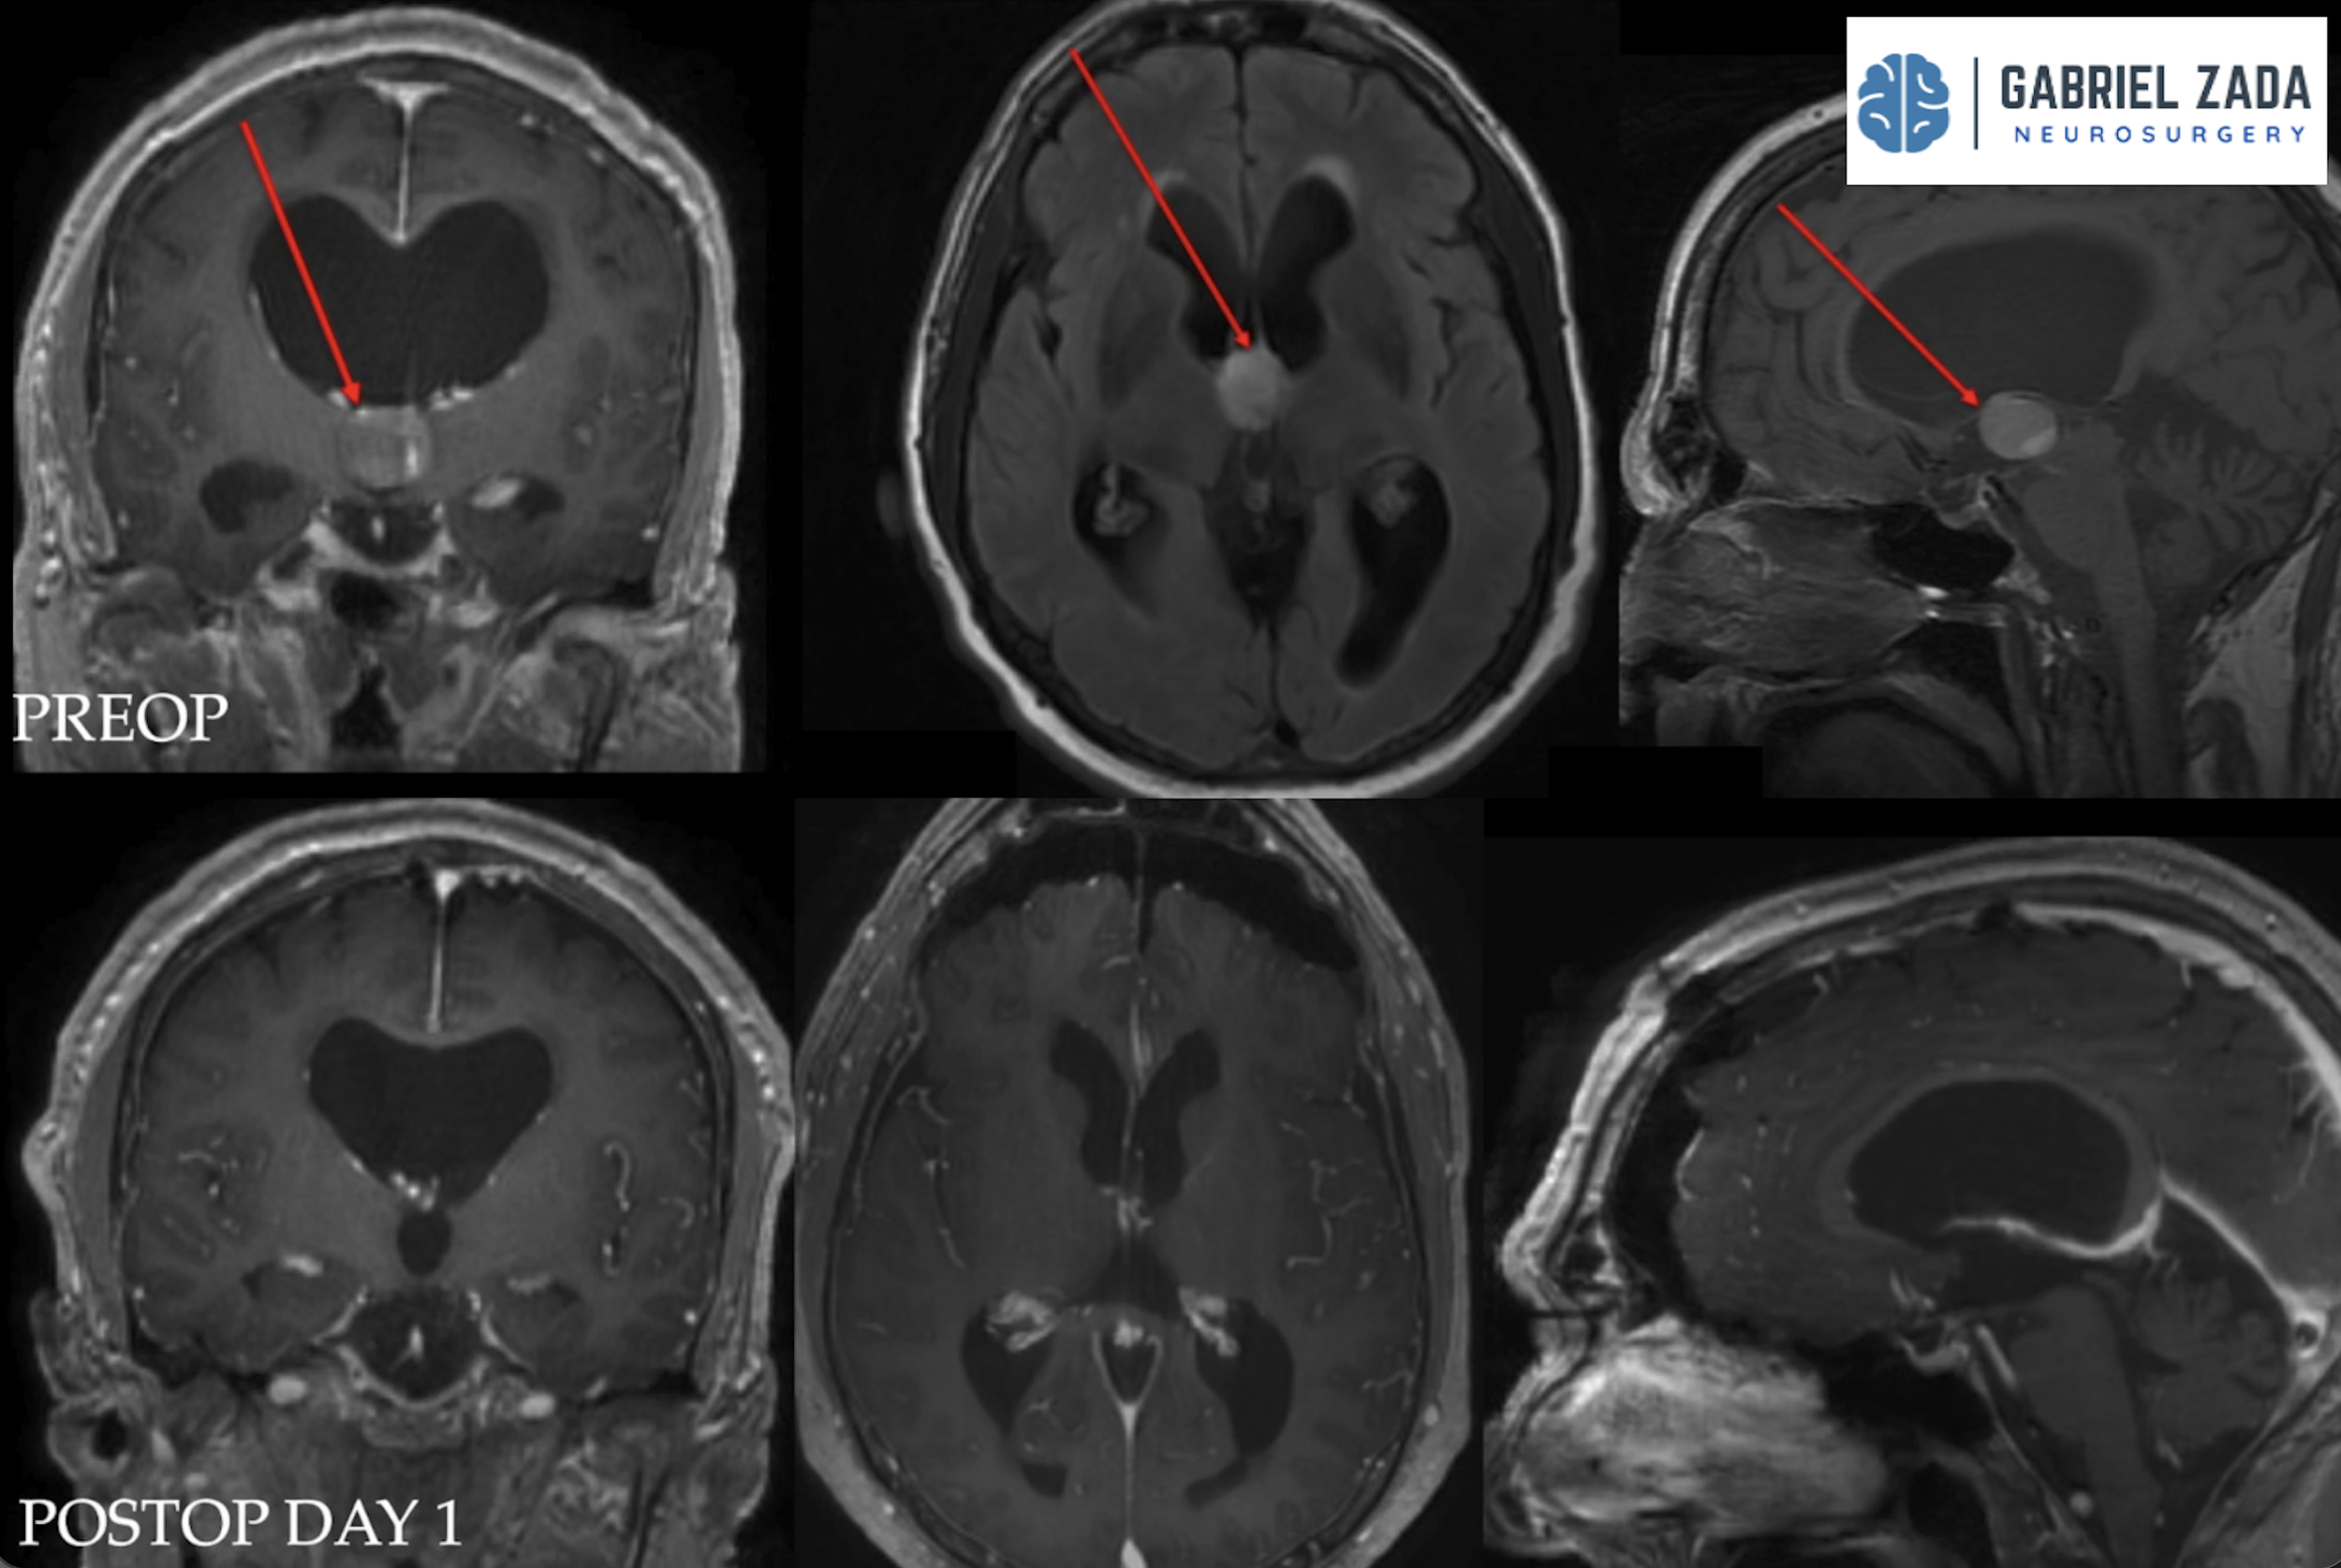

Explore this comprehensive gallery featuring pre‑ and post‑operative imaging of patients with skull‑base tumors treated by Gabriel Zada, MD, MS, FAANS, FACS. These cases highlight Dr. Zada’s expertise in advanced neurosurgical techniques and outcomes.

*Representative cases shown for educational purposes. All images de-identified. Individual results vary.